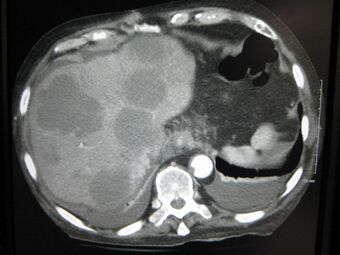

Cross section of a human liver, taken at autopsy examination, showing multiple large pale tumor deposits. The tumor is an adenocarcinoma derived from a primary lesion in the body of the pancreas.

Treatment can consist of surgery (hepatectomy), chemotherapy and/or therapies specifically aimed at the liver like radiofrequency ablation, transcatheter arterial chemoembolization, selective internal radiation therapy and irreversible electroporation. For most patients no effective treatment exists because both lobes are usually involved, making surgical resection impossible. Younger patients with metastases from colorectal cancer confined to one lobe of the liver and up to 4 in number may be treated by partial hepatectomy. In selected cases, chemotherapy may be given systemically or via hepatic artery.

In some tumors, notably those arising from the colon and rectum, apparently solitary metastases or metastases to one or other lobes may be resected. A careful search for other metastases is required, including local recurrence of the original primary tumor (e.g., via colonoscopy) and dissemination elsewhere (e.g., via CT of the thorax). 5-year survival rates of 30-40% have been reported following resection. [citation needed]